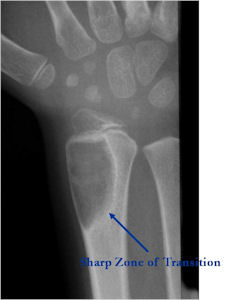

Plain X-rays:

- Geographic, circumscribed lesion usually around 5cm in size.

- There may be expansion of bone, cortical thinning and cortical breakthrough. A soft tissue mass may accompany this lesion but the soft tissue component is usually contained by the periosteum.

- The periosteum remains intact around the soft tissue component. Might need a CT scan to detect the subtle calcification (Egg Shell Rim of Calcification) associated with an intact periosteal reaction

- The lesion may be entirely radiolucent but usually shows some degree of mineralization. Mineralization may appear stippled like cartilage but do not see chondroid pathologically. Mineralization is sometimes better detected on a CT scan rather than an x-ray.

- Usually less surrounding sclerosis than an osteoid osteoma.

- Arise from the Diaphysis (75%) more commonly than Metaphyseal (25%)

- 4 cm to 6 cm in size